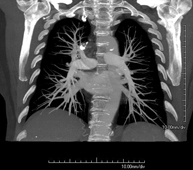

Prueba diagnóstica que consiste en el estudio de las arterias pulmonares mediante el empleo de un equipo de TC (Tomografía Computarizada) obteniendo imágenes bi y tridimensionales. En este estudio es imprescindible el uso de contraste yodado, el cual permitirá una mejor definición anatómica. Esta prueba está principalmente indicada en los casos de sospecha de tromboembolismo pulmonar (TEP) para descartar o confirmar la presencia de coágulos sanguíneos en el interior de las arterias. - TC Tórax alta resolución

Prova diagnòstica que consisteix en l'estudi de les artèries pulmonars mitjançant l'ús d'un equip de TC (Tomografia Computaritzada) i amb l'obtenció d'imatges bi i tridimensionals. En aquest estudis és imprescindible l'ús de contrast iodat, que permet una millor definició anatòmica. Aquesta prova està principalment indicada en els casos en els quals hi hagi sospita de tromboembolisme pulmonar (TEP) per descartar o confirmar la presència de coàguls sanguinis a l'interior de les artèries. - Angio TC cardíac